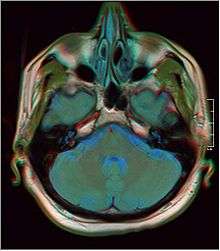

Concha bullosa

A concha bullosa is a pneumatized (air-filled) cavity within a turbinate in the nose.[1] (Concha is another term for turbinate.) Bullosa refers to the air-filled cavity within the turbinate.[1] It is a normal anatomic variant seen in up to half the population. Occasionally, a large concha bullosa within a turbinate may cause it to bulge sufficiently to obstruct the opening of an adjacent sinus, possibly leading to recurrent sinusitis.[1] In such a case the turbinate can be reduced in size by endoscopic nasal surgery (turbinectomy). The presence of a concha bullosa is often associated with deviation of the nasal septum toward the opposite side of the nasal cavity.[2] Although it is thought that sinusitis or sinus pathology has relation to concha bullosa, no strong statistical correlation has been demonstrated.[1]